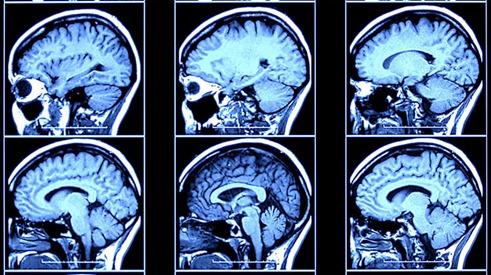

En la dinámica de investigación y búsqueda, con una tendencia permanente para conseguir respuestas que alivien el sufrir humano y aumenten su bienestar, no deben existir hipotecas, censuras u obstáculos económicos, ideológicos o políticos. El descubrimiento de la células madres y sus aplicaciones en medicina se ha matizado con el hallazgo de las “Células de Yamanaka” (Nóbel de medicina 2012) en el que por la inclusión de varios genes específicos en una célula madura normal del organismo humano adulto, da lugar a su transformación en célula embrionaria, es decir con la posibilidad de transformarse en cualquier tipo de célula del organismo y la capacidad constante de multiplicarse en un tiempo hasta ahora no limitado; la reprogramación celular se presenta como prevención y como tratamiento eficaz y eficiente de numerosas patologías crónicas. Las neurociencias están argumentando y formulando la hipótesis de un gen de naturaleza energética con información sobre las inquietudes de trascendencia e inmortalidad comunes al ser humano, y que nos descubren y definen estados de conciencia que señalan nuevas dimensiones en nuestros espacios interiores, y en los que se contemplan los llamados fenómenos místicos, que como todo acontecimiento que sucede en la persona, se encuentra sustentado por estructuras neuronales, químicas y eléctricas localizadas y detectadas anatómicamente por el PET (tomografía por emisión de positrones) o fMRI (resonancia magnética funcional).